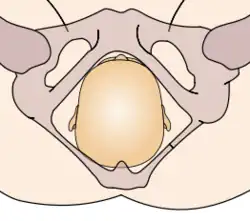

In the vertex presentation, the occiput typically is anterior and thus in an optimal position to negotiate the pelvic curve by extending the head. In an occiput posterior position, labor becomes prolonged, and more operative interventions are deemed necessary.[4] The prevalence of the persistent occiput posterior is given as 4.7%.[4]

The vertex presentations are further classified according to the position of the occiput, both right, left, or transverse and anterior or posterior:

- Left Occipito-Anterior (LOA), Left Occipito-Posterior (LOP), Left Occipito-Transverse (LOT)

- Right Occipito-Anterior (ROA), Right Occipito-Posterior (ROP), Right Occipito-Transverse (ROT)

The occipito-anterior position is ideal for birth; it means that the baby is lined up so as to fit through the pelvis as easily as possible. The baby is head down, facing the spine, with their back anterior. In this position, the baby's chin is tucked onto their chest, so that the smallest part of their head will be applied to the cervix first. The position is usually "Left Occiput Anterior", or LOA. Occasionally, the baby may be "Right Occiput Anterior", or ROA.[5]